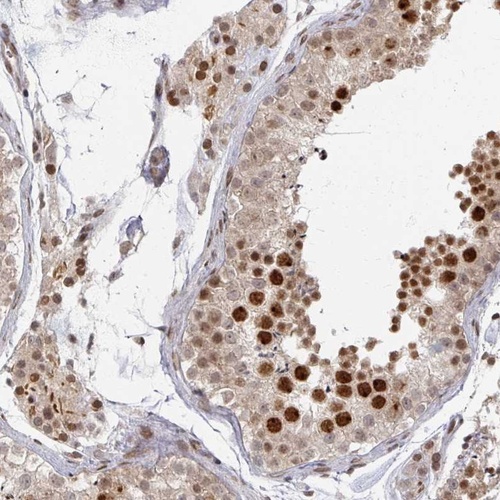

Immunohistochemical staining of human testis shows strong nuclear positivity in cells in seminiferus ducts. Leydig cells displayed strong nuclear and cytoplasmic positivity.